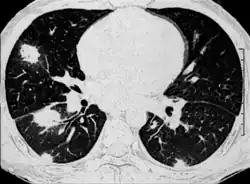

| H&E stain showing a fungal pneumonia (pulmonary aspergillosis) | |